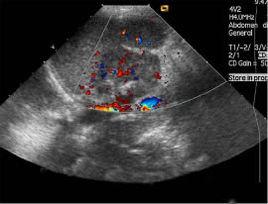

都卜勒彩超功能介紹

為國內乃至國際上最高檔的彩超,除具有普通彩超的功能外,其獨有的優良性能主要體現在以下幾方面: